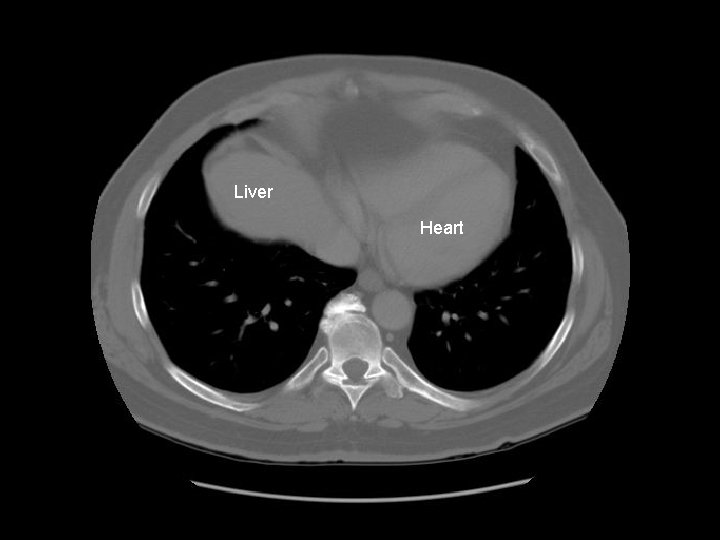

Liver Heart